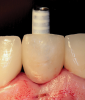

(50.) An opaqued titanium abutment was placed on the implant, and the natural tooth shell was then bonded to the abutment with flowable composite in the incisal half.

Figure 50